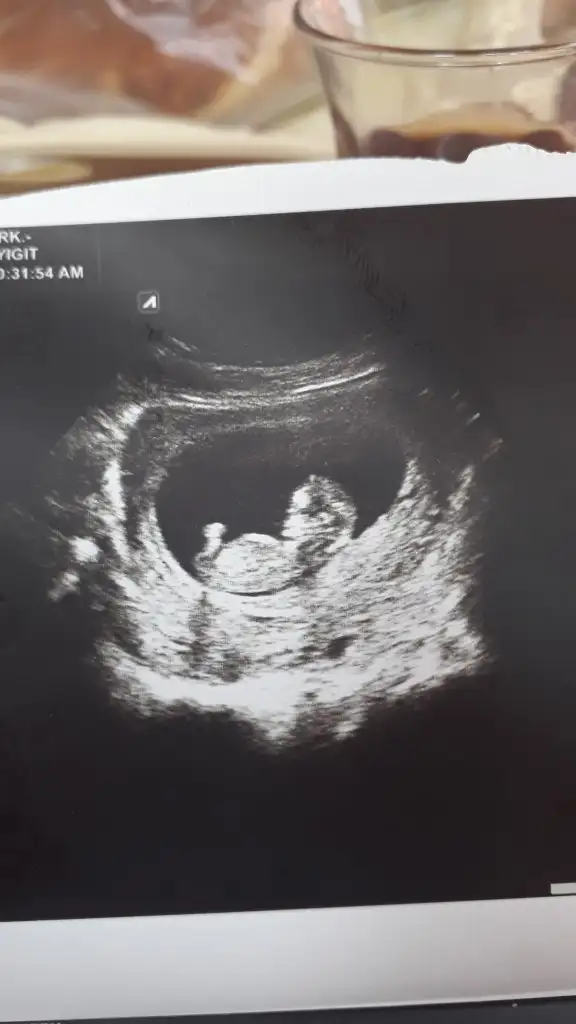

Ikiz bebislerime tahmin yapabilirmisinz kizlar 😊

Kizlar bu benim minigimin 9+4 karindan ultrason goruntusu. Erken ama cok merak ediyorum. Cinsiyet tahmini yapacak olaniniz var mi:) Eki Görüntüle 2275542

Erkek gibi geldi canim😊😊 Rabbim gonlune gore hayirlisini sagliklisini pamuk gibisini versin insallahhh🤩 konuma goreyi sanirim 7.hafta ultrason goruntusune gore soyluyolar🤗

Konu sahibi öğrenmişsiniz ama ben de ilk gördüğümde kız olduğunu tahmin etmiştim çünkü ilk haftalarda kese görüntüsü yuvarlaksa kız, fasülye gibi yayvansa daha çok erkek diyorlardı. Aynı anda 5 arkadaş hamile kaldık. Sadece benimki erkekti. Tesadüf mü bilmiyorum ama hepimizin ilk haftalardaki ultrason görüntülerimizde benimki hariç onlarınki hep yuvarlaktı, benimkiyse fasülye gibi yayvandı. Tabi sonradan cinsiyetleri öğrendiğimizde bize epeeyy garip gelmişti :)